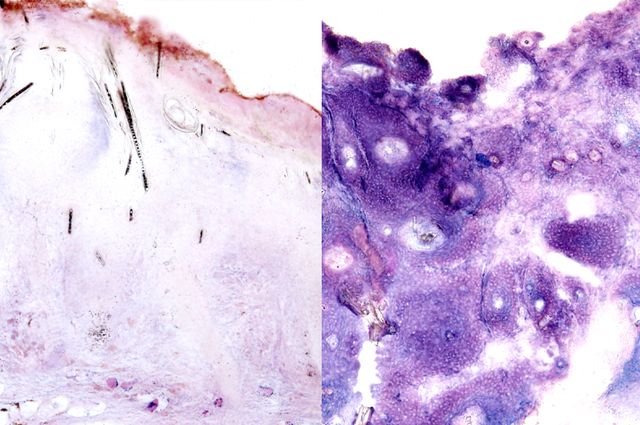

Scientists at the Eli and Edythe Broad Center of Regenerative Medicine and Stem Cell Research at UCLA have discovered that squamous cell skin cancers do not require increased glucose to power their development and growth, contrary to a long-held belief about cancer metabolism.

The findings could lead to a better understanding of the metabolic needs of many different types of cancer, and to the development of new cancer treatments. The research, led by senior authors Heather Christofk and Bill Lowry, was published in the journal Nature Communications.